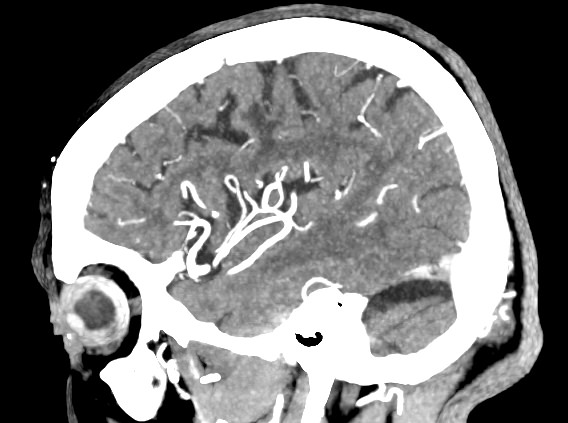

Мультиспиральная компьютерная томография головного мозга относится к лучевым методам исследования и основана на использовании проникающей способности рентгеновских лучей, которые в различной степени поглощаются органами и тканями. Степень поглощения зависит от плотности анатомических структур, благодаря чему можно получить подробные изображения внутренних органов. Во время исследования трубка томографа вращается вокруг пациента и производит снимки поперечного сечения, что позволяет детально визуализировать кости черепа и все структуры головного мозга.

Для улучшения видимости внутричерепных структур применяется методика внутривенного болюсного контрастирования. Во время проведения КТ пациенту в вену вводится йодсодержащее контрастное вещество. Контраст с током крови попадает в патологически измененные участки ткани и очаги, что на снимках придает им яркие отличительные признаки по сравнению с окружающими здоровыми тканями. Контрастирование, в первую очередь, помогает в диагностике опухолевых процессов на ранних стадиях, когда лечение может дать наилучший результат.

В наших медицинских центрах КТ головного мозга с контрастированием проводится на новейших мультиспиральных компьютерных томографах экспертного уровня TOSHIBA AQUILION в различных модификациях. Аппараты снабжены увеличенным количеством сверхчувствительных детекторов, что позволяет при сканировании выполнять множество срезов поперечного сечения с минимальной толщиной среза от 0,5 мм. В результате получаются изображения исследуемой зоны в мельчайших подробностях, которые затем с помощью инновационных цифровых приложений преобразуются в трехмерные пространственные модели головного мозга для более точной диагностики. Помимо высокого качества изображений увеличенное количество детекторов обеспечивает быстроту выполнения сканирования, что значительно снижает уровень рентгеновского облучения для пациента во время обследования.